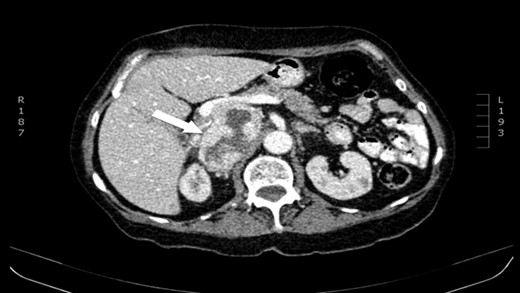

The authors report a case of a 64-year-old female, with no relevant family history and a past medical history of recently diagnosed supraventricular tachycardia, arterial hypertension, type 2 diabetes mellitus, euthyroid multinodular goiter and chronic venous insufficiency. She was referred to our Institution from other Hospital where she went due to paroxysms of palpitations, headache and diaphoresis, that led to biochemical investigation that was remarkable for: total plasmatic cathecolamines: 73 747 ng/L (normal range (NR) <598 ng/L), plasmatic noradrenaline: 73 589 ng/L (NR <420 ng/L), adrenaline: 130 ng/L (NR <84 ng/L), plasmatic dopamine: 28 ng/L (NR <94ng/L), aldosterone: 87,5 ng/dL (NR 4–31 ng/dL), plasmatic renin activity: 33 ng/mL/h (NR 0,5–4 ng/mL/h), Vanylmandelic acid: 39,2 mg/24 h (NR <13,6 mg/24 h). Abdominal contrast enhanced CT scan revealed a large (70 × 35×78 mm3), hyperdense (20 HU) right adrenal mass. Abdominal magnetic resonance (MRI) also described an adrenal mass with 66×33 mm2, suggestive of pheocromocitoma (slightly hypointense on T1 and markedly hyperintense on T2 weighted imaging). No vascular nor locoreginal lymph node involvement were found and the left adrenal was radiologically normal. The patient underwent genetic testing with next generation sequencing, that excluded mutations of the succinate dehydrogenase (SDHB, C, D and A), MEN2, VHL, Neurofibromatosis type 1 genes. Genetic testing for MAX and TMEM127 were not performed due to institutional unavailability. Pre-operative pharmacological therapy was initiated with phenoxybenzamine (10 mg twice a day), followed by bisoprolol (20 mg/day) and amlodipine (5 mg/day), which rendered the patient fit for surgery. The patient underwent transperitoneal laparoscopic right adrenalectomy. Intraoperatively, a hipervascularized right adrenal gland with adhesions to the upper pole of the kidney was identified and excised, with no complications recorded. In the immediate post-operative period, antihypertensive drugs were stopped and blood pressure remained normal until the second post-operative day, when hypertension and tachycardia recurred, leading to urinary metanephrine reevaluation on the 10th post-operative day. The results were highly suggestive of disease persistence (urinary normetanephrines >10 500 ng/L (NR <600 ng/L)). Histology revealed no signs of neoplasia. Abdominal CT scan revealed the persistence of a solid heterogeneous nodule, with 70 × 49 × 87 mm3 (AP × T × L) adjacent to upper right renal pole, with peripheral contrast enhancement and central necrosis (Figs 1–3). This findings suggested abdominal paraganglioma (of the organ of Zuckerkandl). Due to the higher malignant potential of paragangliomas, an 123I-MIBG scintigraphy was performed, excluding metastatic disease.

CT scan (coronal) of the heterogenous solid nodule adjacent to upper inner right renal pole (white arrow).